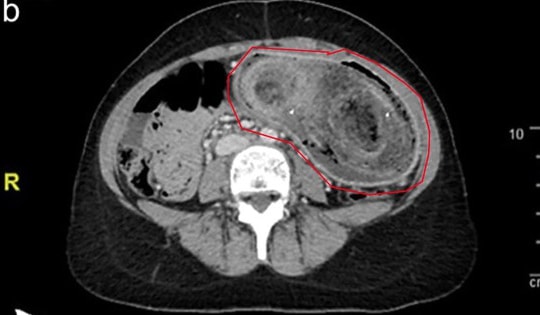

Các bác sĩ đã phát hiện ra khối u quái dài 12 cm trong bụng cô gái 18 tuổi, bên trong còn chứa 24 chiếc răng với nhiều hình dạng khác nhau.